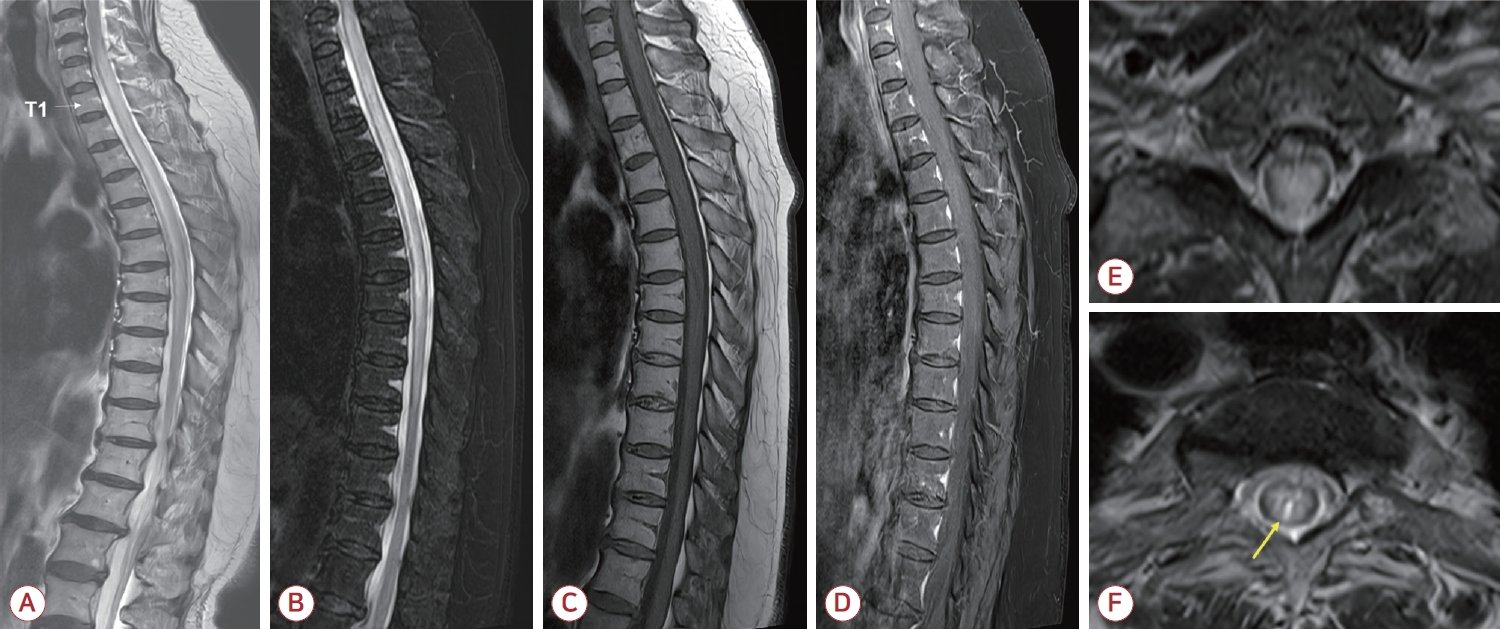

척수MRI 검사를 통하여 척수 횡단면을 거의 다 침범하는 경추 6번분절부터 흉추 9번분절에 이르는 세로로 매우 긴 T2 고신호강도와 T1 저신호강도, 척수부종을 확인하였다(Fig.). NMOSD에서 특징적인 brighter spotty lesion (BSL)도 관찰되었으나 조영증강은 없었다. 뇌척수액 분석에서는 백혈구 19/mm3, 적혈구 211/mm3, 단백질 26.1 mg/dL, 포도당 79 mg/dL (혈청 포도당 193 mg/dL)였다. 면역글로불린-G지수는 0.6이었고 올리고클론띠는 음성이었다. 항수초희소돌기아세포당단백질항체(항myelin oligodendrocyte glycoprotein [MOG]항체)는 음성이었다. 항아쿠아포린4항체 검사는 지속적으로 모두 양성(positive [1+] in 1:10; MFIr, 7.65; positive cut-off >1.40)이었다. 척수염 재발로 진단하였고 5일간 고용량(1 g/day) 메틸프레드니솔론 정맥 주사 투여 후 경구 스테로이드로 전환하면서 환자는 재활 병원으로 퇴원하였다. 퇴원 2주 후 외래 진찰 시 EDSS 1.5점으로 약간 호전된 상태였다. 이에 경구 스테로이드 10 mg/day로 유지하면서 아자싸이오프린을 50 mg/day 용량으로 추가하였고 점차 증량하기로 계획하였다.

본 증례의 환자는 67세에 비정형 증상과 짧은 길이의 척수염 병터, 항체 양성을 통해 NMOSD이 처음 진단된 늦은 발병(late-onset) 환자에 속한다. 재발 역시 척수염이었으나 처음의 척수염과는 전혀 다른 영상 특징을 보였는데 10개의 척추분절에 달하는 세로로 매우 긴 병변과 중심회색질을 침범하는 넓은 횡단면 병변, 척수부종, BSL 등은 NMOSD에 부합하는 반면 조영증강은 관찰되지 않았다. 임상 증상도 MRI 병터에서 예상되는 심한 운동장애나 방광기능장애를 보이지 않고 하지 이상 감각으로 인한 보행 불안정성 정도만 호소하였으며 천천히 독립 보행이 가능한 수준으로 비교적 낮은 EDSS를 보여 영상과 임상 소견이 일치하지 않았다.